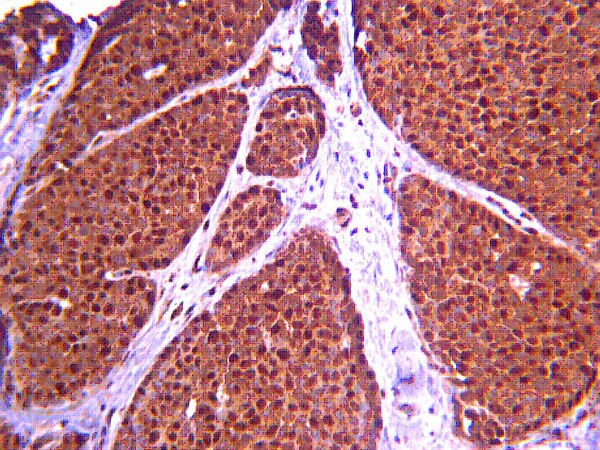

Reactive oxygen species (ROS), in particular, H(2)O(2), is essential for full activation of VEGF receptor2 (VEGFR2) signaling involved in endothelial cell (EC) proliferation and migration. Extracellular superoxide dismutase (ecSOD) is a major secreted extracellular enzyme that catalyzes the dismutation of superoxide to H(2)O(2), and anchors to EC surface through heparin-binding domain (HBD). Mice lacking ecSOD show impaired postnatal angiogenesis. However, it is unknown whether ecSOD-derived H(2)O(2) regulates VEGF signaling. Here we show that gene transfer of ecSOD, but not ecSOD lacking HBD (ecSOD-DeltaHBD), increases H(2)O(2) levels in adductor muscle of mice, and promotes angiogenesis after hindlimb ischemia. Mice lacking ecSOD show reduction of H(2)O(2) in non-ischemic and ischemic limbs. In vitro, overexpression of ecSOD, but not ecSOD-DeltaHBD, in cultured medium in ECs enhances VEGF-induced tyrosine phosphorylation of VEGFR2 (VEGFR2-pY), which is prevented by short-term pretreatment with catalase that scavenges extracellular H(2)O(2). Either exogenous H(2)O(2) (>500 microM), which is diffusible, or nitric oxide donor has no effect on VEGF-induced VEGFR2-pY. These suggest that ecSOD binding to ECs via HBD is required for localized generation of extracellular H(2)O(2) to regulate VEGFR2-pY. Mechanistically, VEGF-induced VEGFR2-pY in caveolae/lipid rafts, but non-lipid rafts, is enhanced by ecSOD, which localizes at lipid rafts via HBD. One of the targets of ROS is protein tyrosine phosphatases (PTPs). ecSOD induces oxidation and inactivation of both PTP1B and DEP1, which negatively regulates VEGFR2-pY, in caveolae/lipid rafts, but not non-lipid rafts. Disruption of caveolae/lipid rafts, or PTPs inhibitor orthovanadate, or siRNAs for PTP1B and DEP1 enhances VEGF-induced VEGFR2-pY, which prevents ecSOD-induced effect. Functionally, ecSOD promotes VEGF-stimulated EC migration and proliferation. In summary, extracellular H(2)O(2) generated by ecSOD localized at caveolae/lipid rafts via HBD promotes VEGFR2 signaling via oxidative inactivation of PTPs in these microdomains. Thus, ecSOD is a potential therapeutic target for angiogenesis-dependent cardiovascular diseases. Full Text Article | 20422004